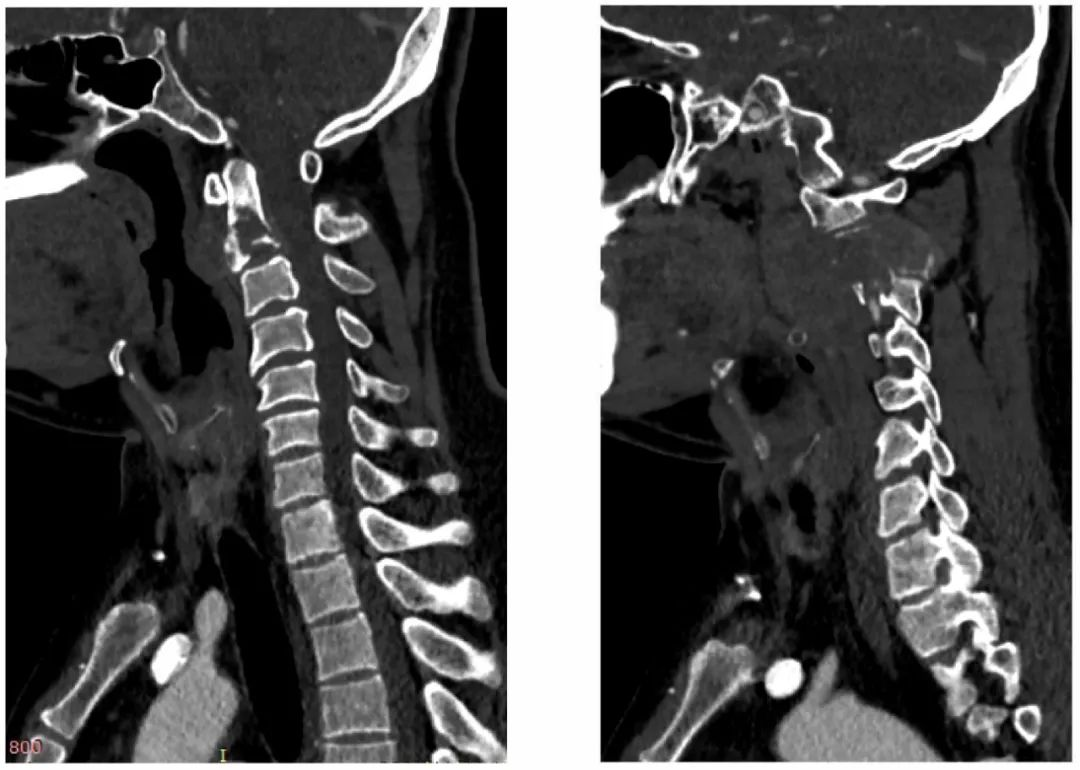

病史:male, 63 y/o

Neck pain for 3 months

影像资料:

诊断:C2椎体肿瘤